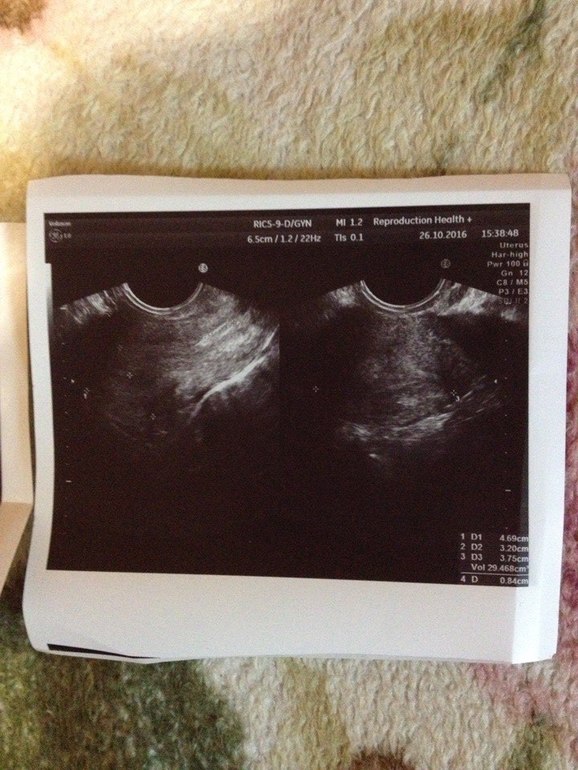

Девочки,может,кто понимает в узи?

Узистка сказала ничего нет в матке..Да и толком вообще ничего не говорила..я спросила: а внематочной есть риск? в ответ: Я не знаю. Через месяц приходите-посмотрим...Я в тихом ужасе..Не знаю что делать..22 ДЗ..

Лада, к сожалению на представленом узи-фото действительно не видно плодного яйца. Но вы не паникуйте раньше времени, может еще появится.